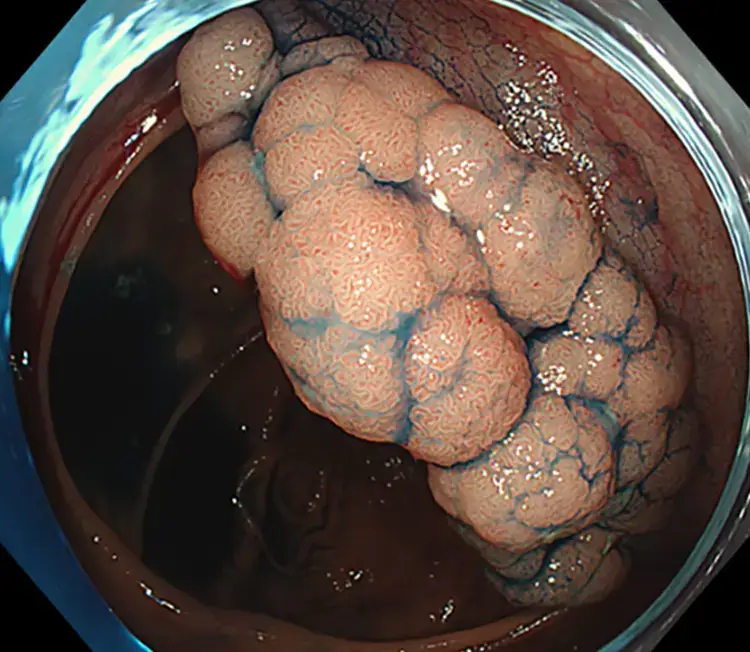

This is a large, 6cm ascending colon tumour which was successfully resected by EMR.